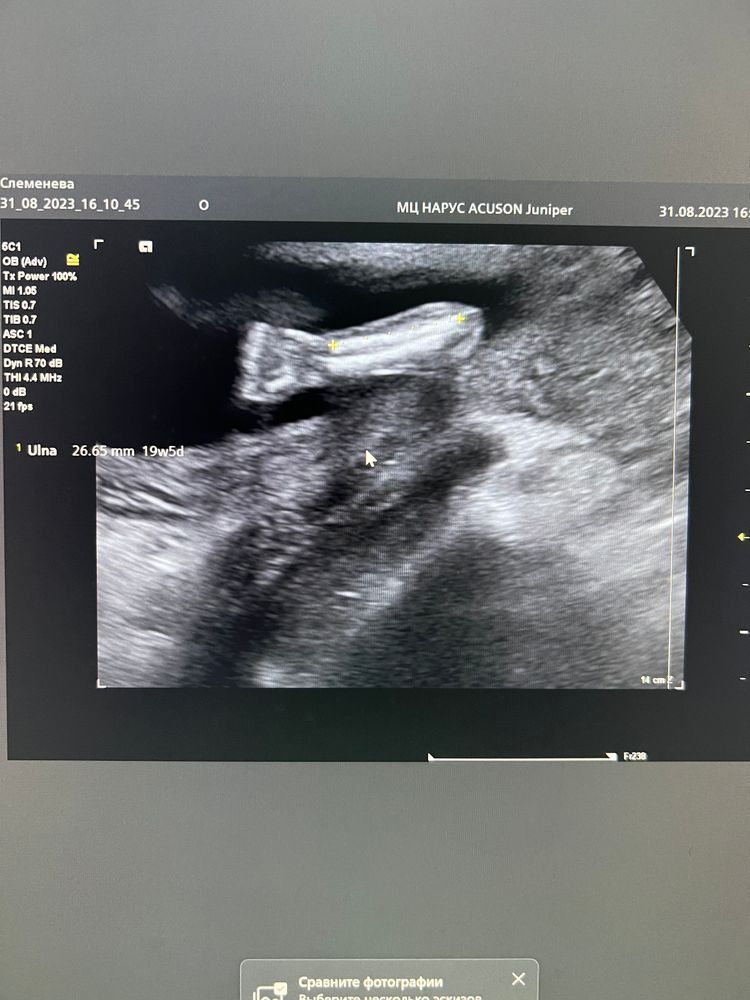

Второй скрининг

По результатам все хорошо - срокам соответствуем. Немного пугает шейка матки. На первом скрининге была 47мм, на втором 37 мм. Укорочение на 1см за 7 недель, получается. К врачу 6 сентября, посмотрим что скажет.